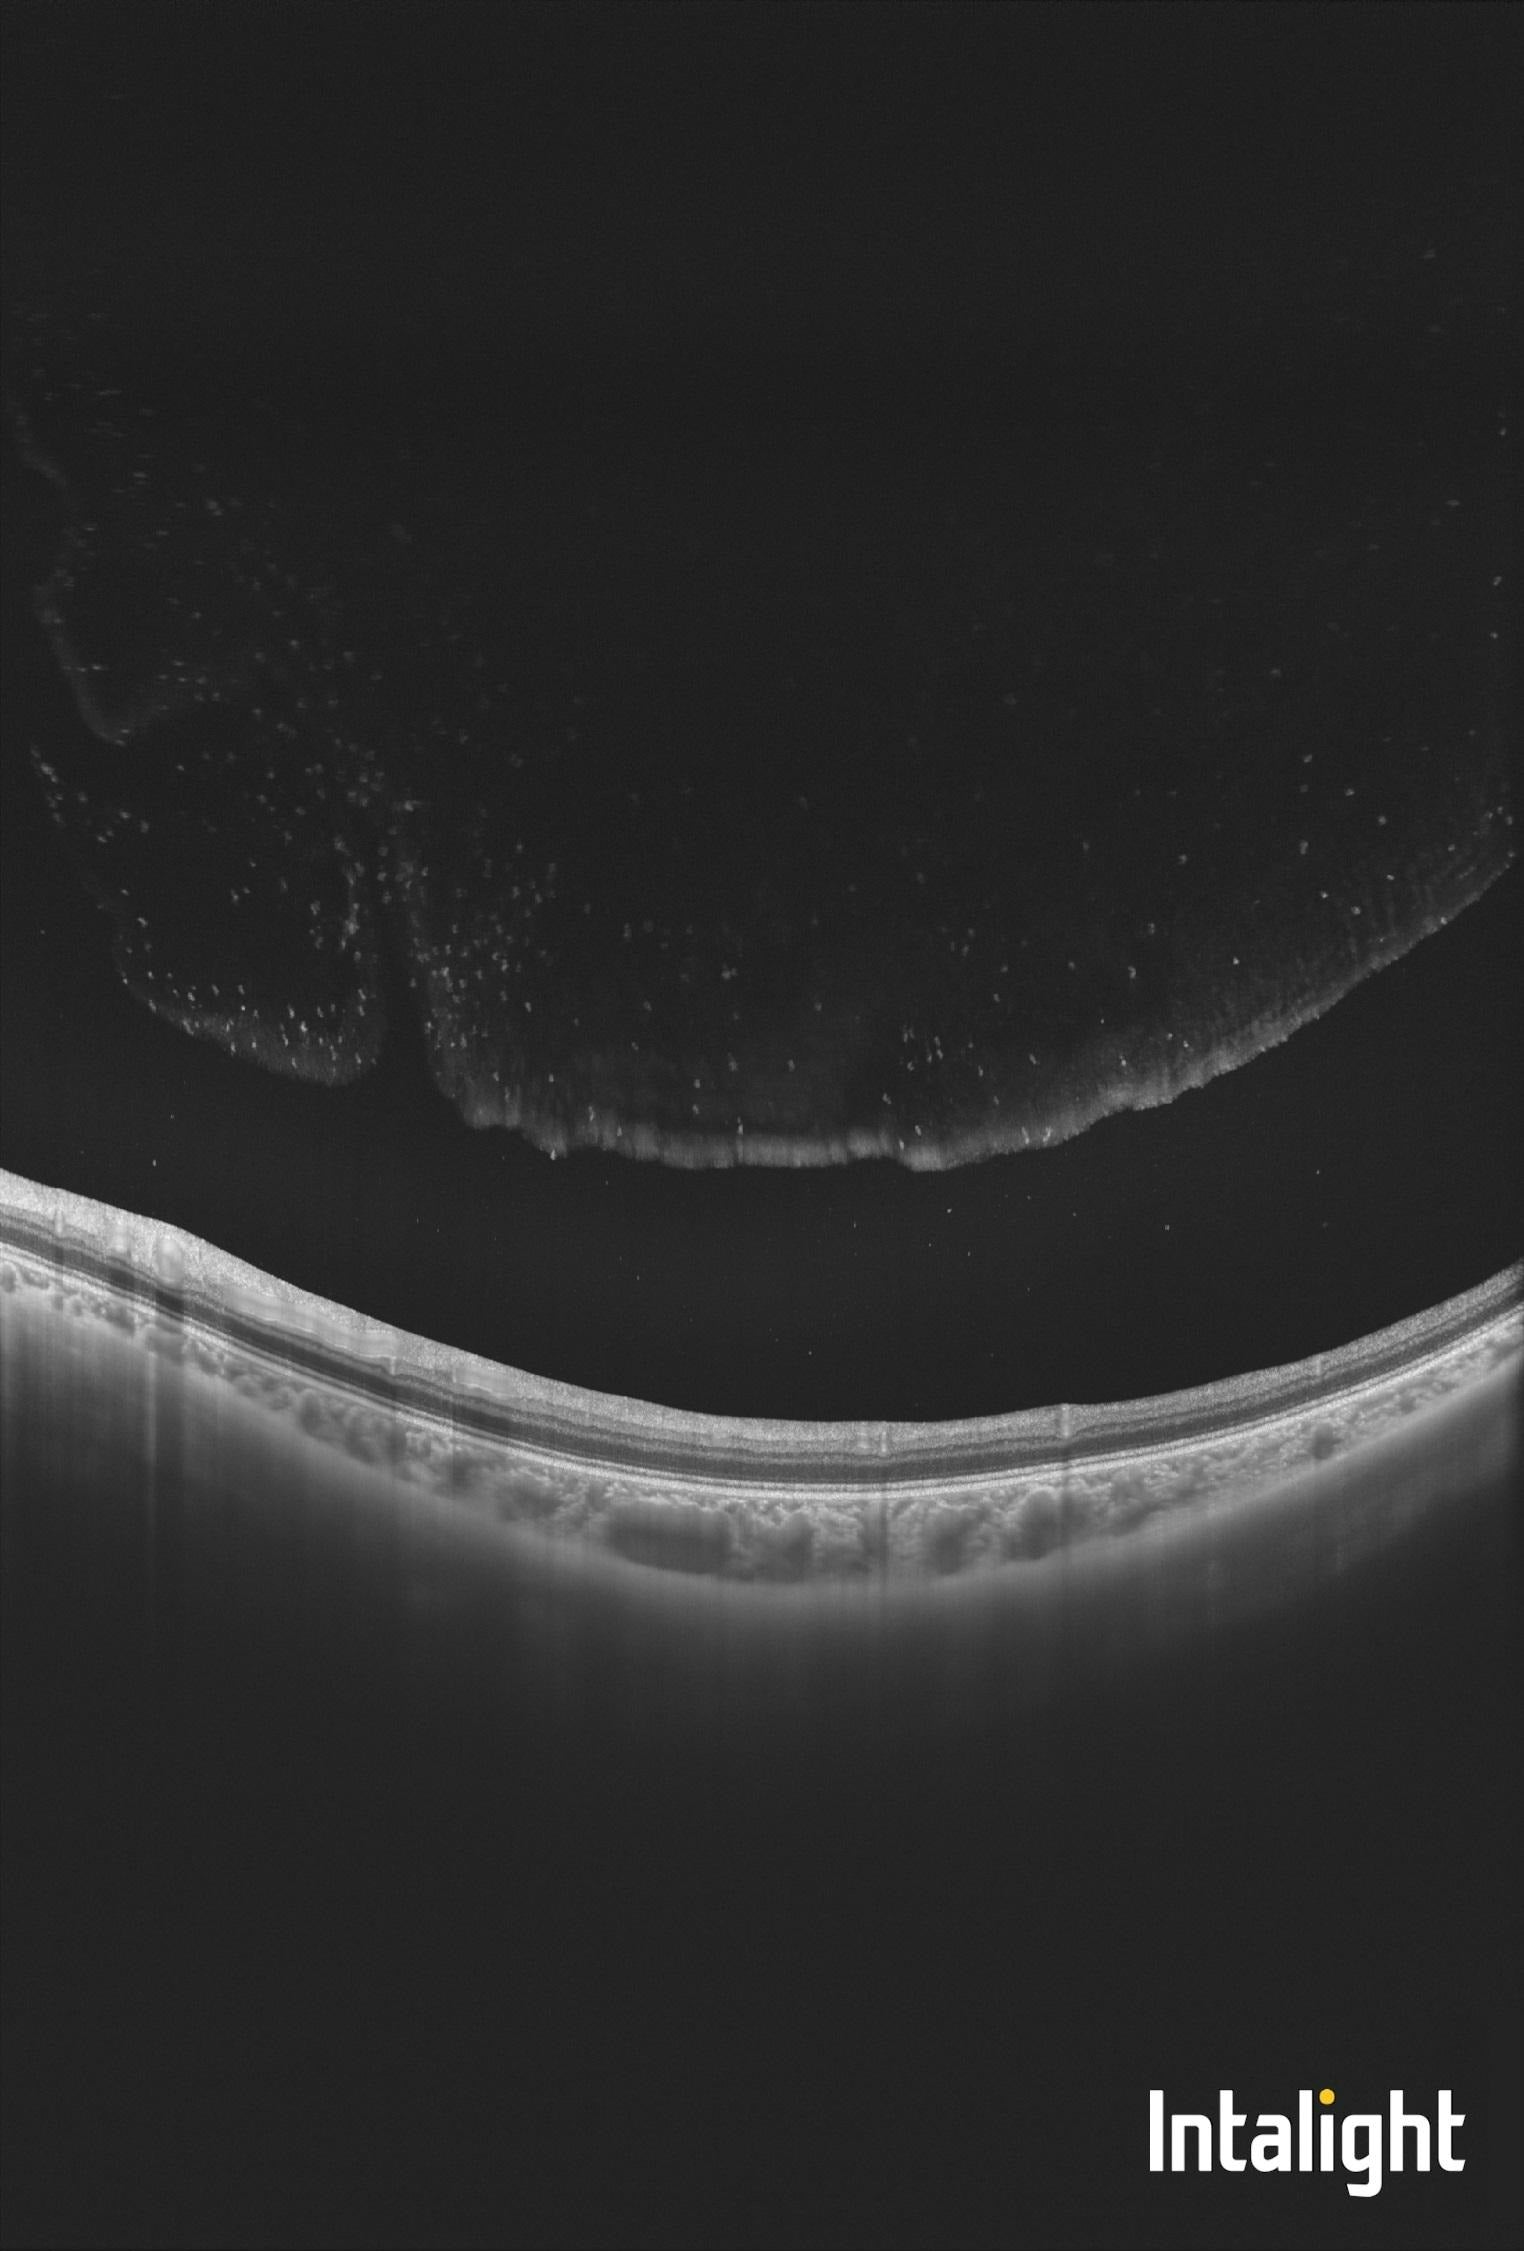

Uveitída - synechie po zápalových procesoch v oku

Synechie, zrasty dúhovky k rohovke alebo šošovke, zachytené pomocou štrbinovej lampy S390L.